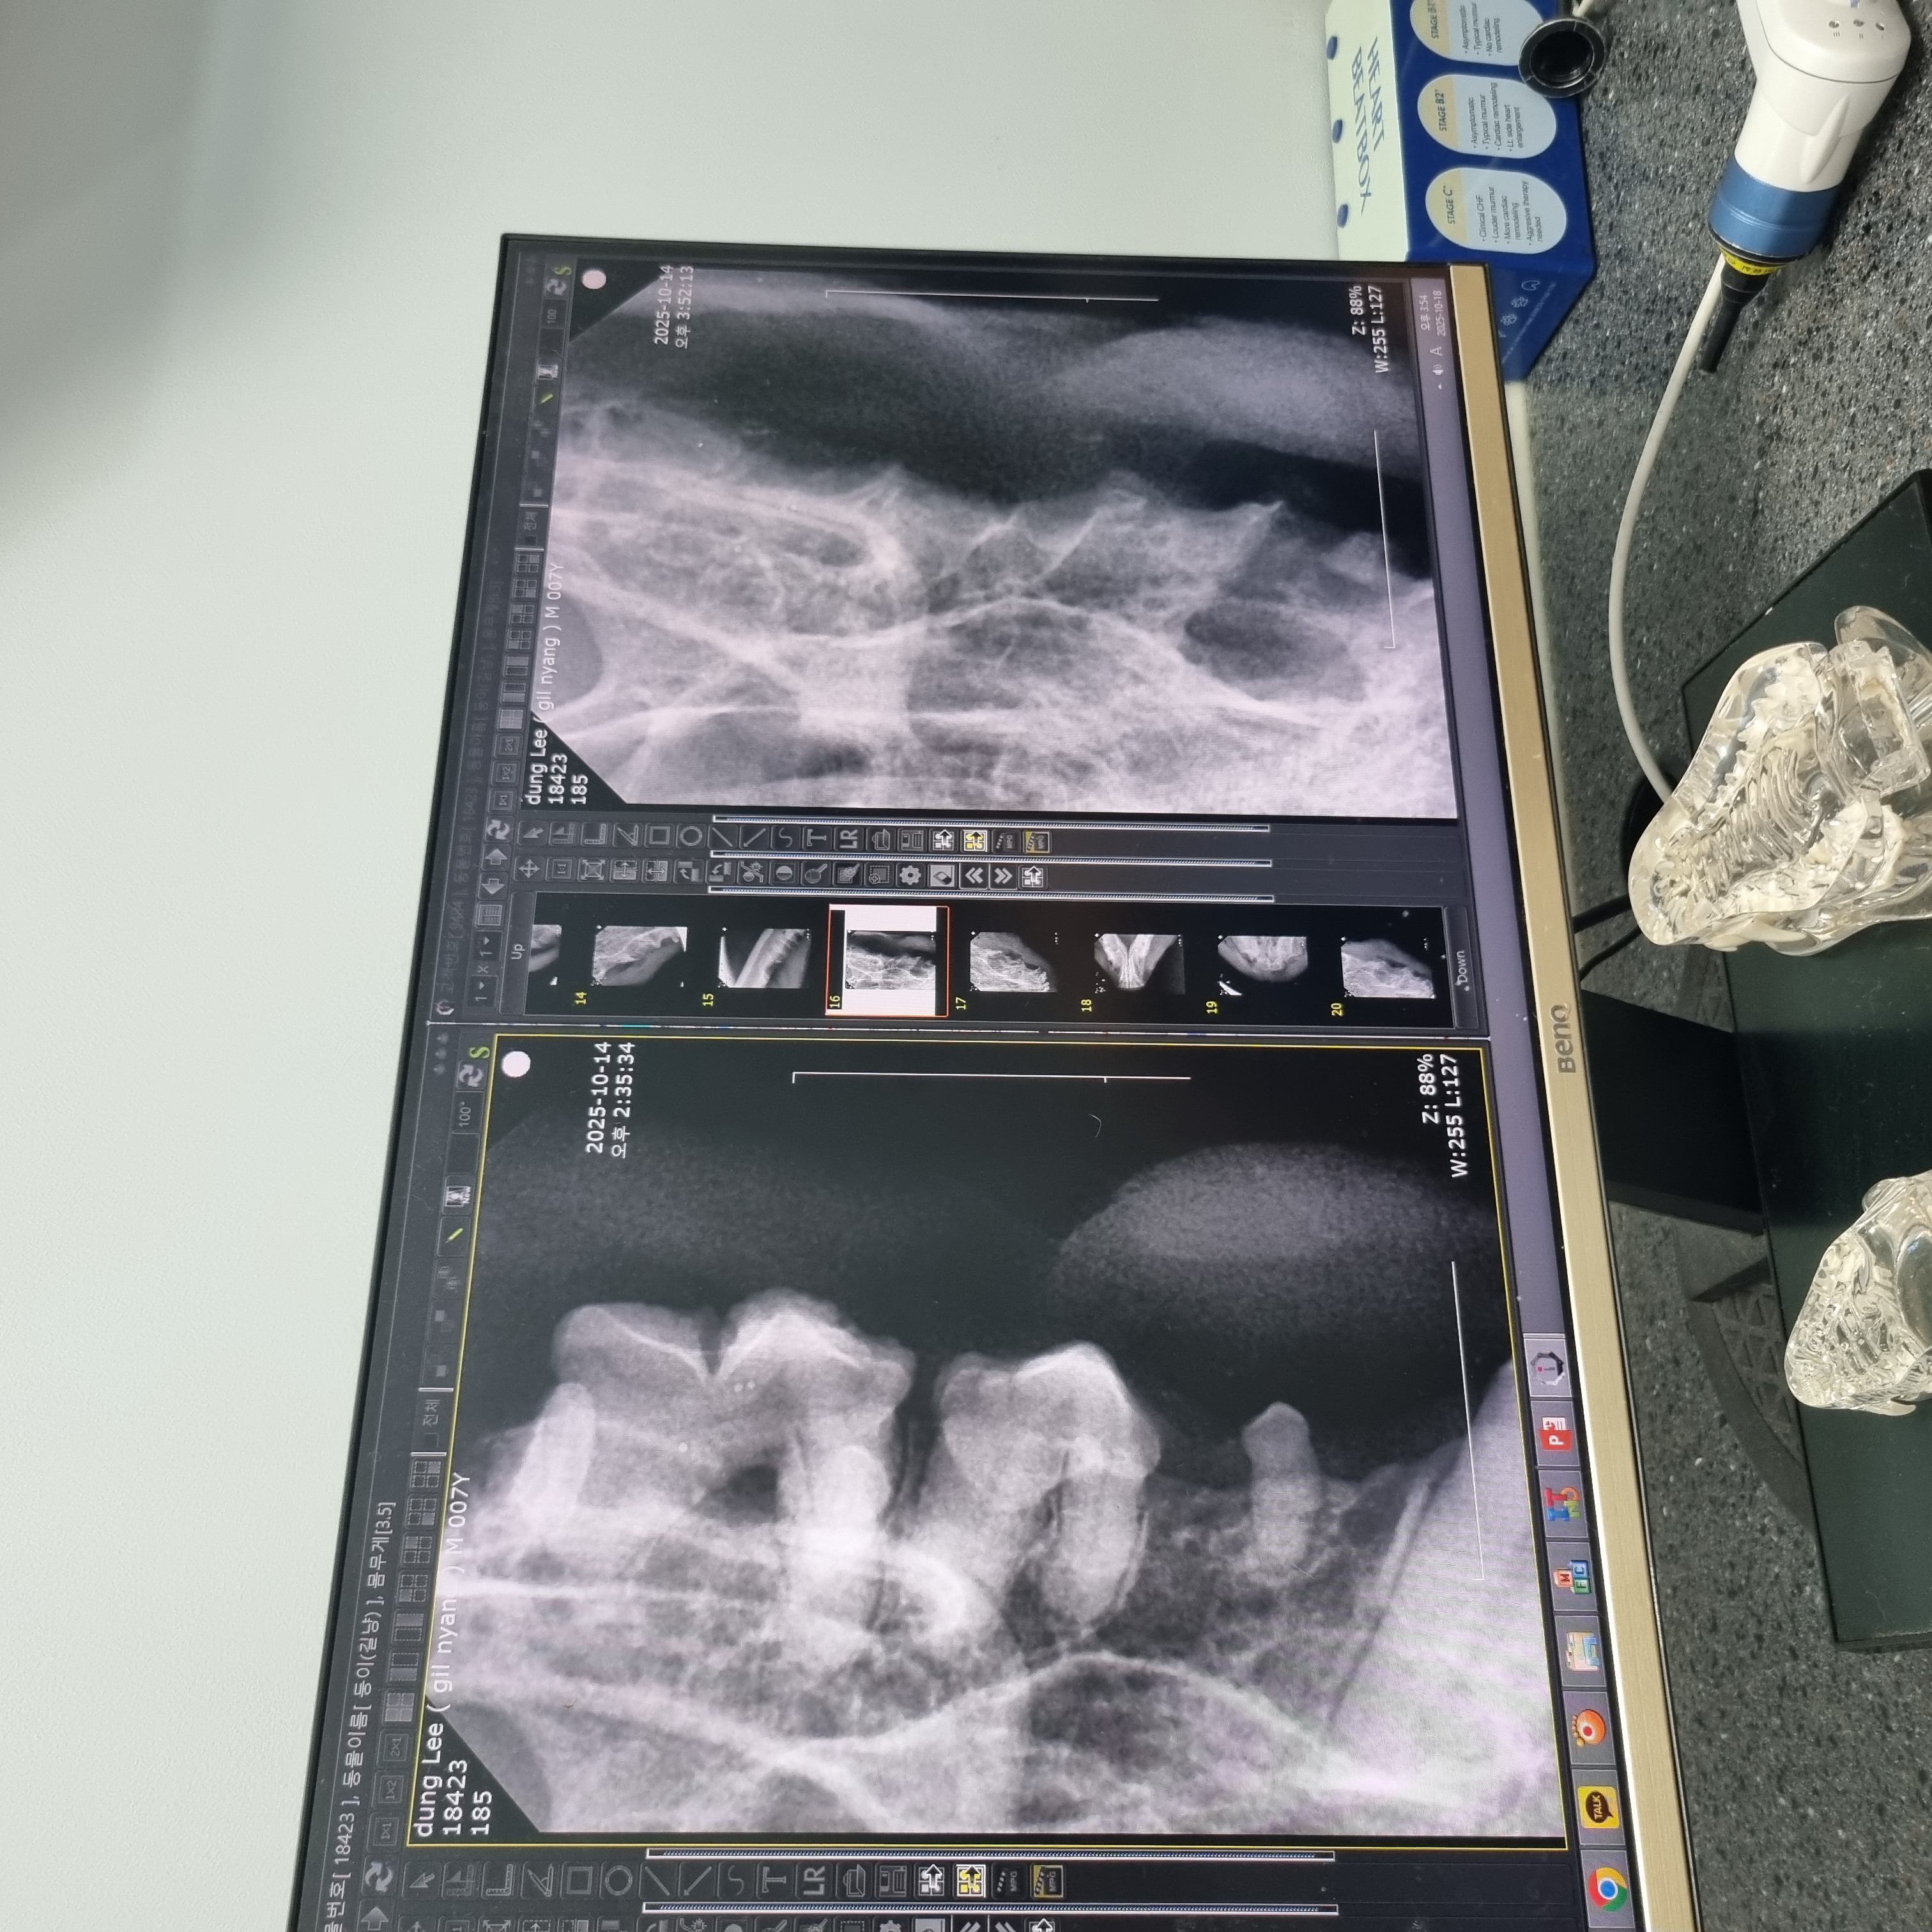

| 치료과정 | 츄르나 파우치를 먹을 때 아주 크게 왕!! 하고 짖는 등 고통을 호소하고 작년보다 최소 2~3킬로는 빠진 모습이라 급히 치료지원신청을 하였고 당일 둥이 구조에도 성공했습니다 둥이는 10월 4일에 구조하게 되었고 이후 병원에 내원하여 정확한 상태를 확인받았습니다. 우리 둥이 마취 후 입 안을 보니 전발치를 해야하는 아주 전형적인 증상이라고 사진을 보여주셨습니다. 둥이의 목구멍 주위에 동그랗고 빨갛게 부은 염증부터 삭아버린 이빨... 얼마나 고통스러웠을지 사진을 보고 마음이 너무 아팠어요. 둥이의 수술을 위해 혈액검사와 키트검사 등을 진행하고 전발치수술을 하게 되었습니다. 수술 이후에는 병원에서 송곳니까지 깨끗하게 전발치한 사진을 치아엑스레이를 찍어 상세하게 보여주셨습니다. 수술을 마친 이후에는 병원에 입원시켜서 수액 처치도 받고 회복에 전념하였습니다. 둥이는 며칠전에 면회때만 해도 좀처럼 기운이 없어 여러 걱정이 많았는데 다행히 어제 면회 때는 기력을 되찾은 모습입니다. 큰 소리로 야옹거리기도 하고 입원실 밖도 돌아다니고 먹고 아주 조금 남은 습식사료까지 싹싹 핥아먹는 모습을 보였습니다. |